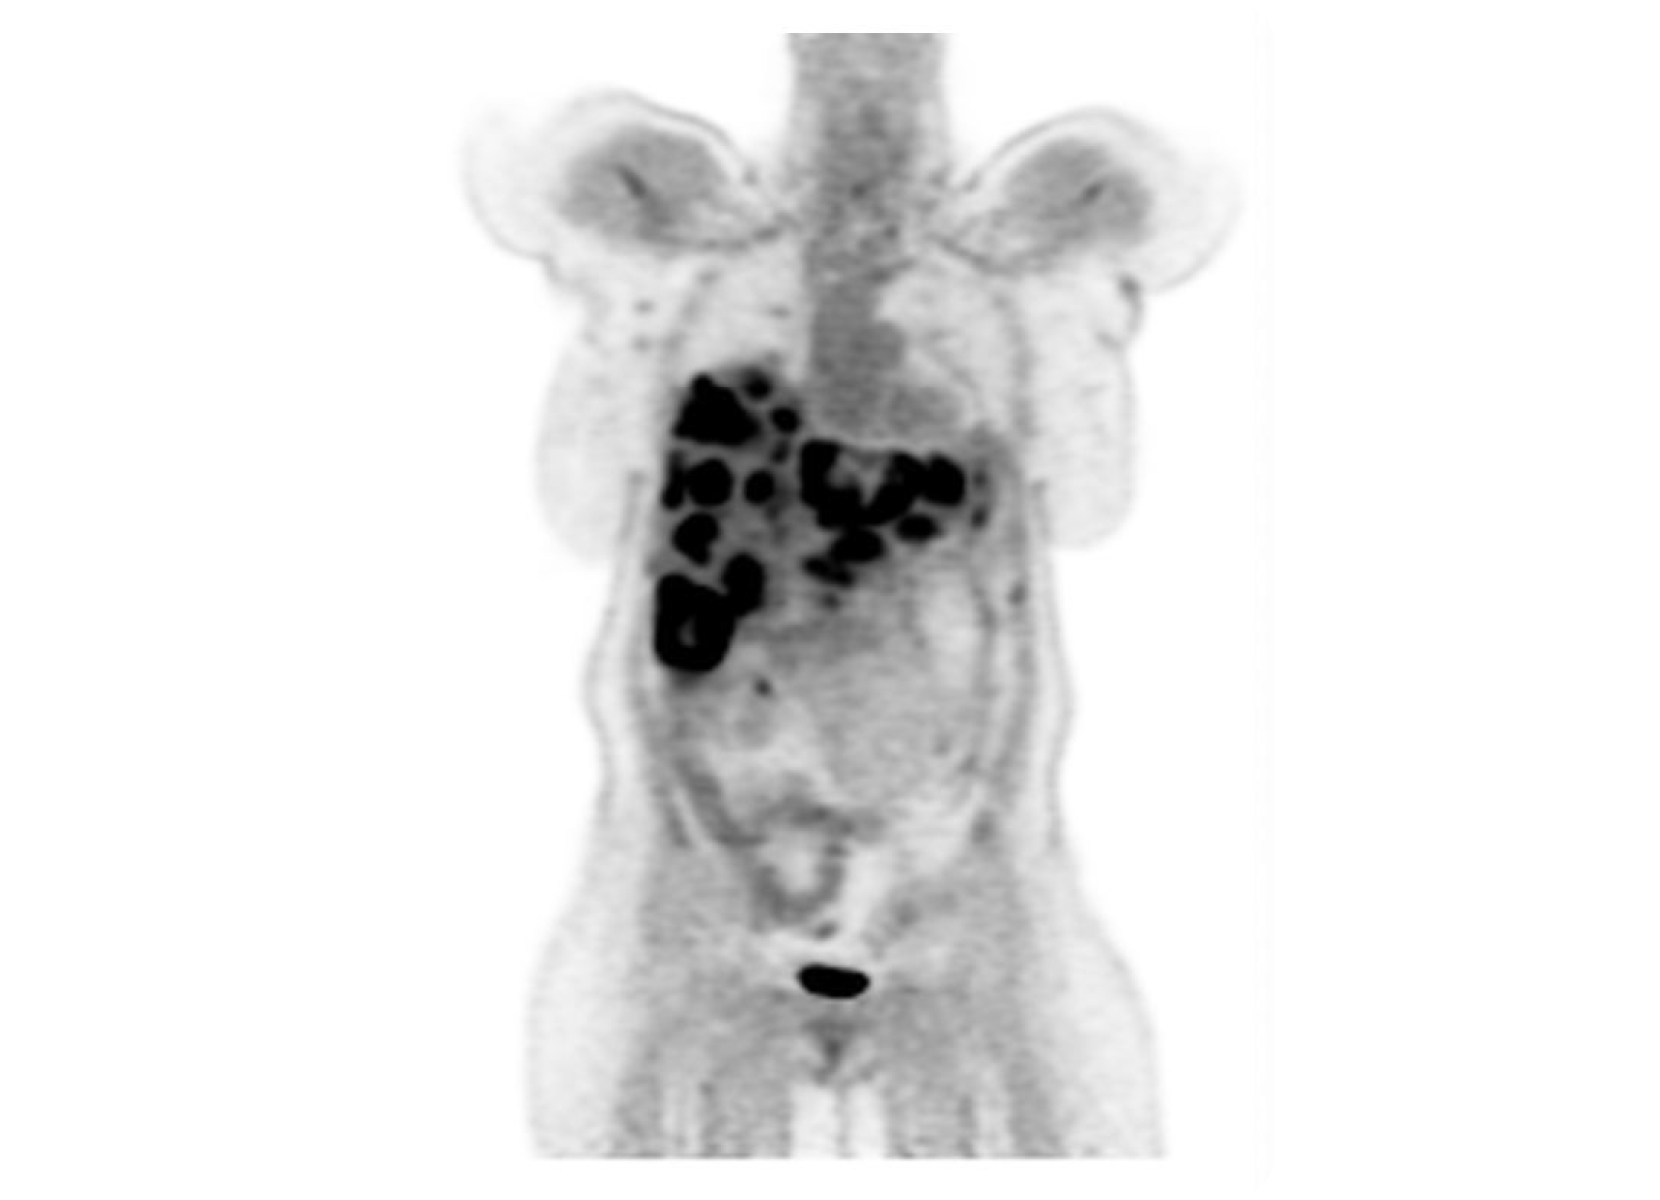

Conventional

ACQ TIME:

20 min

SubtleHD™(PET)

5 min

18F-Florbetapir (AMYLOID)

Philips Vereos PET/CT